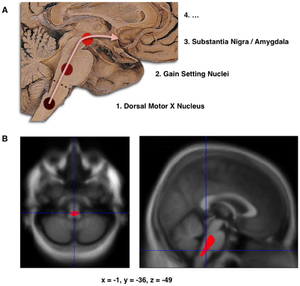

Composite of three images, one in top row (referred to in caption as A), two in second row (referred to as B). Top shows a mid-line sagittal plane of the brainstem and cerebellum. There are three circles superimposed along the brainstem and an arrow linking them from bottom to top and continuing upward and forward towards the frontal lobes of the brain. A line of text accompanies each circle: lower is "1. Dorsal Motor X Nucleus", middle is "2. Gain Setting Nuclei" and upper is "3. Substantia Nigra/Amygdala". The fourth line of text above the others says "4. ...". The two images at the bottom of the composite are magnetic resonance imaging (MRI) scans, one sagittal and the other transverse, centred at the same brain coordinates (x=-1, y=-36, z=-49). A colored blob marking volume reduction covers most of the brainstem.

A. Schematic initial progression of Lewy body deposits in the first stages of Parkinson's disease, as proposed by Braak and colleagues

B. Localization of the area of significant brain volume reduction in initial PD compared with a group of participants without the disease in a neuroimaging study, which concluded that brainstem damage may be the first identifiable stage of PD neuropathology[56]

Brain cell death

There is speculation of several mechanisms by which the brain cells could be lost.[57] One mechanism consists of an abnormal accumulation of the protein alpha-synuclein bound to ubiquitin in the damaged cells. This insoluble protein accumulates inside neurones forming inclusions called Lewy bodies.[21][58] According to the Braak staging, a classification of the disease based on pathological findings, Lewy bodies first appear in the olfactory bulb, medulla oblongata and pontine tegmentum, with individuals at this stage being asymptomatic. As the disease progresses, Lewy bodies later develop in the substantia nigra, areas of the midbrain and basal forebrain, and in a last step the neocortex.[21] These brain sites are the main places of neuronal degeneration in PD; however, Lewy bodies may not cause cell death and they may be protective.[57][58] In people with dementia, a generalized presence of Lewy bodies is common in cortical areas. Neurofibrillary tangles and senile plaques, characteristic of Alzheimer's disease, are not common unless the person is demented.[55]